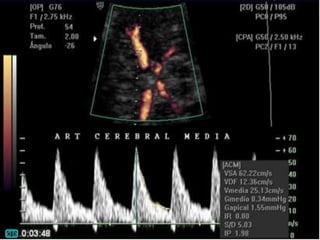

VELOCIMETRIA DOPPLER

•Arteria cerebral media

Fase Silente

Fase de aumento de la resistencia de

arteria umbilical

Fase de centralización Inicial “circuito

de ahorro cerebral”

Fase de centralización avanzada

Fase de descentralización o falsa

normalización